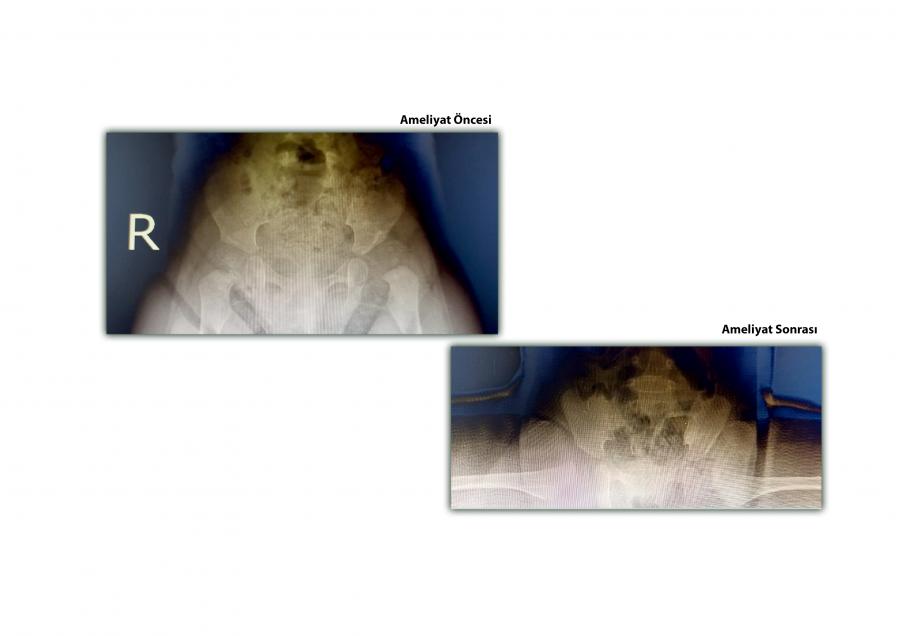

Halk arasında doğuştan kalça çıkığı olarak da bilinen gelişimsel kalça displazisi (GKD) tanısı ile takip edilen 11 aylık kız hastanın sol kalçasına konservatif (ameliyat dışı) yöntemlerle tedavi uygulandı. Yapılan tedaviye cevap vermeyen hastaya KTÜ Farabi Hastanesi Ortopedi Uzmanı Doç. Dr. M. Emre Baki ve ekibi tarafından açık redüksiyon ameliyatı ve pelvipedal alçılama uygulaması başarıyla yapıldı.